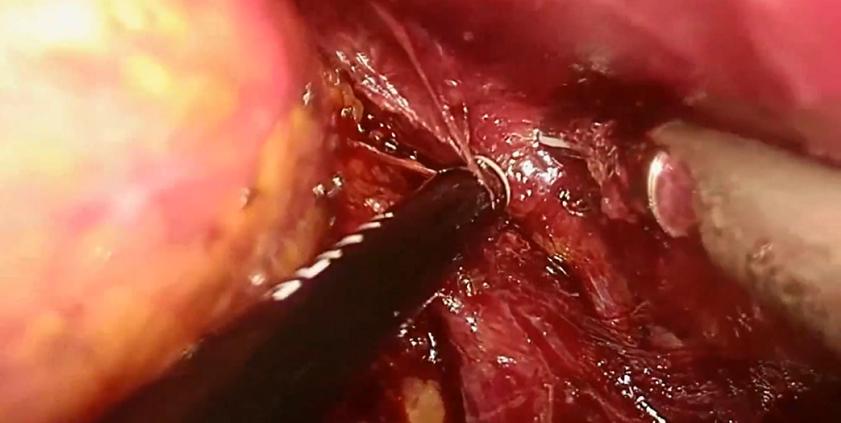

肾上腺肿瘤的下腔静脉瘤栓较为少见,本手术过程中意外发现中央静脉及下腔静脉瘤栓,术中隐约可见瘤栓在下腔静脉里漂荡,可能因瘤栓较细,术前CT难以发现。 由于右侧中央静脉太短,经反复尝试无法通过直接钳夹完整取栓后,术者最终选择切开血管取栓。后腹腔空间小且手术部位位置深,下腔静脉取栓手术难度较高。原则上应阻断瘤栓的近端及远端,但考虑到经后腹腔阻断瘤栓近心端下腔静脉操作困难,难以进行,故选择结扎切断两根肝短静脉、阻断瘤栓远端下腔静脉,然后调高气腹压以对抗减低了的腔静脉压,以达到少出血甚至不出血的目的。 手术演示